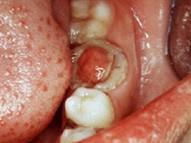

问题 慢性增生性牙髓炎的特点是息肉 ( )

选项 A.与牙髓相连 B.与牙周膜相连 C.与牙槽骨相连 D.充满整个龋洞 E.与牙龈相连

答案 A